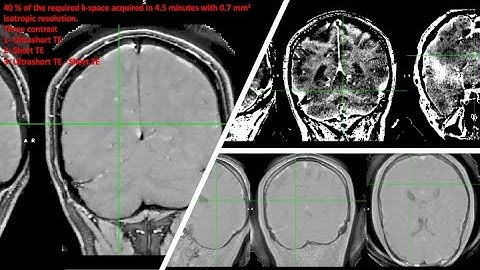

Quantitative Susceptibility Mapping (QSM) High-resolution UTE MRI with Rosette k-space Pattern ISMRM